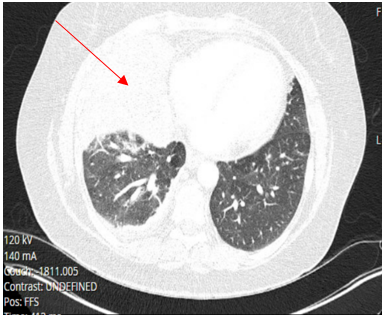

Laboratory testing was notable for elevated WBC, 19.5 (4.0-10.5 K/UL), neutrophils 78.3%, lymphocytes 7.7%, Monocytes 13.5%, eosinophils 0.2%, basophils 0.3%, Procalcitonin 1.46 ng/ml (reference range :< 0.25 ng/ml), SARS-COV 2 was negative. Blood culture, sputum culture, urine strep and legionella urine Antigens were negative, and the upper respiratory PCR panel was negative. MRSA PCR negative. Chest-X ray revealed a consolidation within the right lower lung field, while the CT Chest Angiography showed no evidence of acute pulmonary embolus. Furthermore, there was a progression of consolidative changes in the right middle lobe, traces of right pleural effusion, mild bilateral lower lobe atelectasis, and rounded opacity in the posterior left lower lobe measuring 10 mm. On the same note, there was rounded opacity in the right lower lobe measuring 13 mm, which was a new finding from the prior imaging study, and prominent mediastinal and hilar lymph nodes with the right paratracheal lymph node measuring 13 mm and right hilar lymph node measuring 19 mm (Figure 3 and 4).

Figure 4. CT chest angiography on Hospital admission showing complete right middle lobe consolidation with trace right pleural effusion.